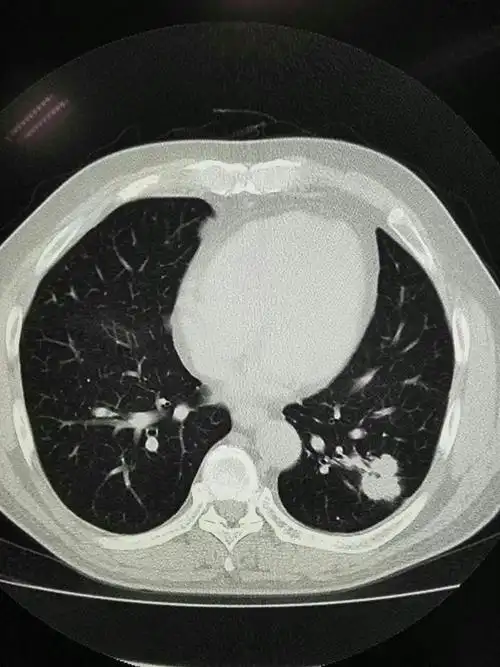

近心端空洞,与气管相通,无强化——肺结核.